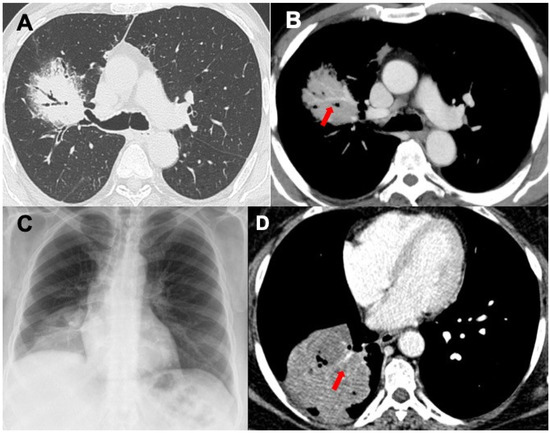

3.1. Consolidations

3.2. Nodules and Masses

- Vincent, J.M.; Ng, Y.Y.; Norton, A.J.; Armstrong, P. CT “angiogram sign” in primary pulmonary lymphoma. J. Comput. Assist. Tomogr. 1992, 16, 829–831. [Google Scholar] [CrossRef] [PubMed]

| MALT | Consolidations, bronchovascular distribution without topographic predominance, lobar-like pneumonia (rare), ±bulging fissure sign, ±angiogram sign, ±air bronchogram; less frequently nodules, masses and GGO; interstitial involvement (very rare) | Neoplasms, lobar or focal atelectasis, infections (Klebsiella pneumoniae), OP, LIP, NLH, sarcoidosis |

| DLBCL | Masses and nodules, mediastinal nodes enlargement, GGO | Neoplasms, LYG, metastasis |